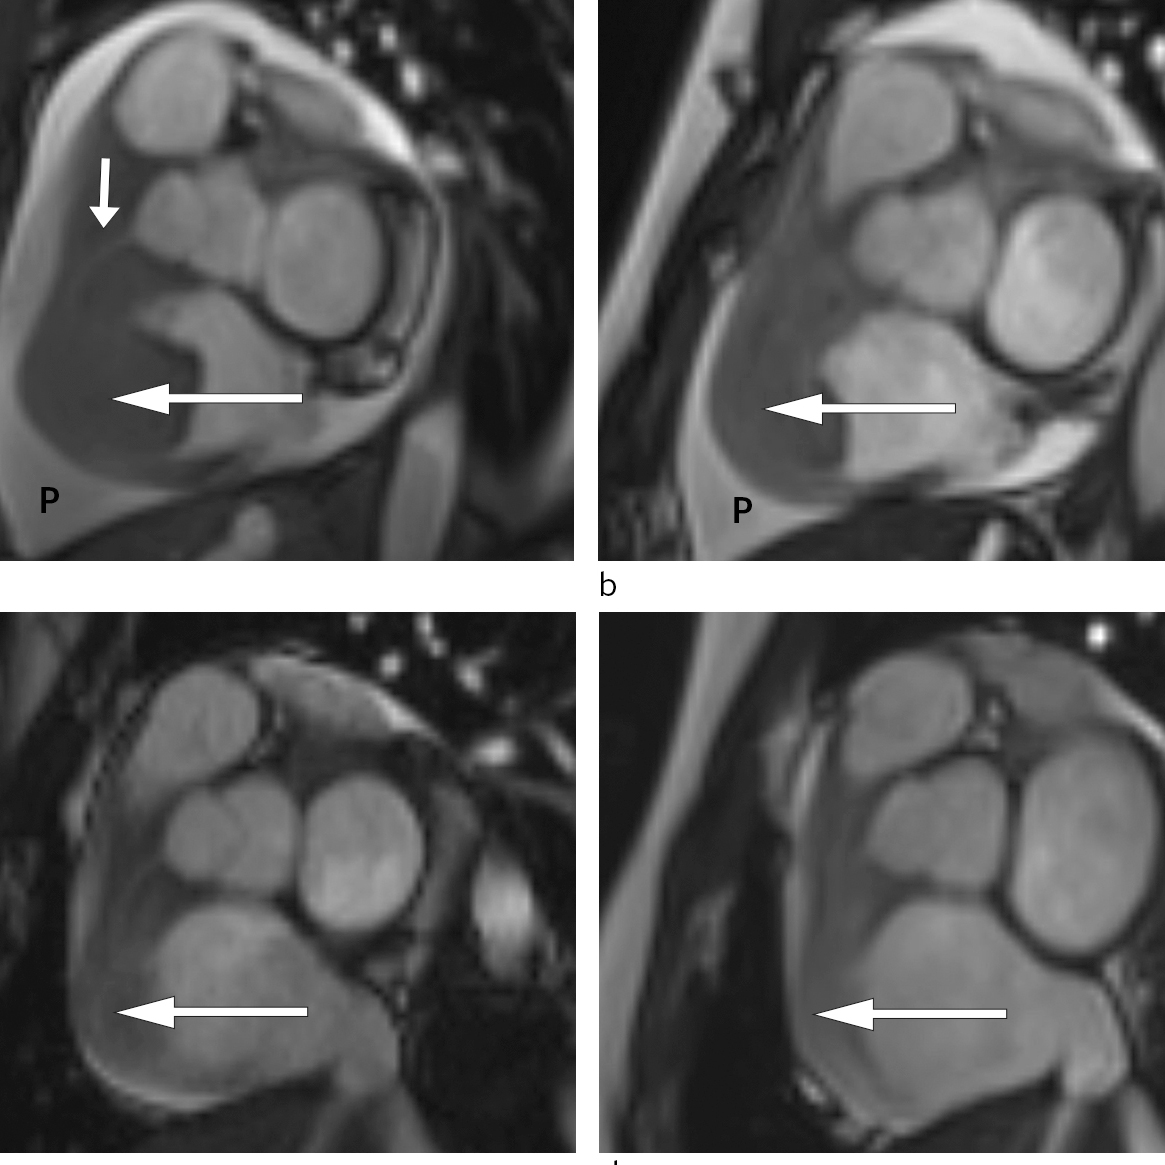

Allereie timar etter at behandlinga tok til merka pasienten avtakande brystsmerter og mindre dyspné. To dagar seinare var det mogleg gjennomføre MR-undersøking av hjartet. Denne bekrefta persisterande tumormassar i høgre atrium og høgre ventrikkel med gjennomvekst av ventrikkelvegg og samanlodding av trikuspidalsegla (fig 3).

Pasienten vart i denne fasen observert i hjarteovervakingsavdelinga. Det vart ikkje observert arytmiar eller andre komplikasjonar til behandlinga. Ho fekk lågdosert fraksjonert heparin som tromboseprofylakse. Repetert MR-undersøking som vart gjort tre dagar etter oppstart med CHOP-regimet, viste betydeleg regress av oppfyllinga i høgre hjartehalvdel og nærast total regress av intrakavitære komponentar. Den atrioventrikulære opninga på høgre side var betydeleg større enn ved den initiale MR-undersøkinga (fig 3).

Pasienten gjennomgjekk ytterlegare blokkurbehandling. Radiologisk evaluering etter andre behandling viste nærast total regress av tumormanifestasjonat i abdomen (fig 3). Ein har heldt fram med R-CHOP-regimet, som har helde sjukdomen i remisjon sidan.